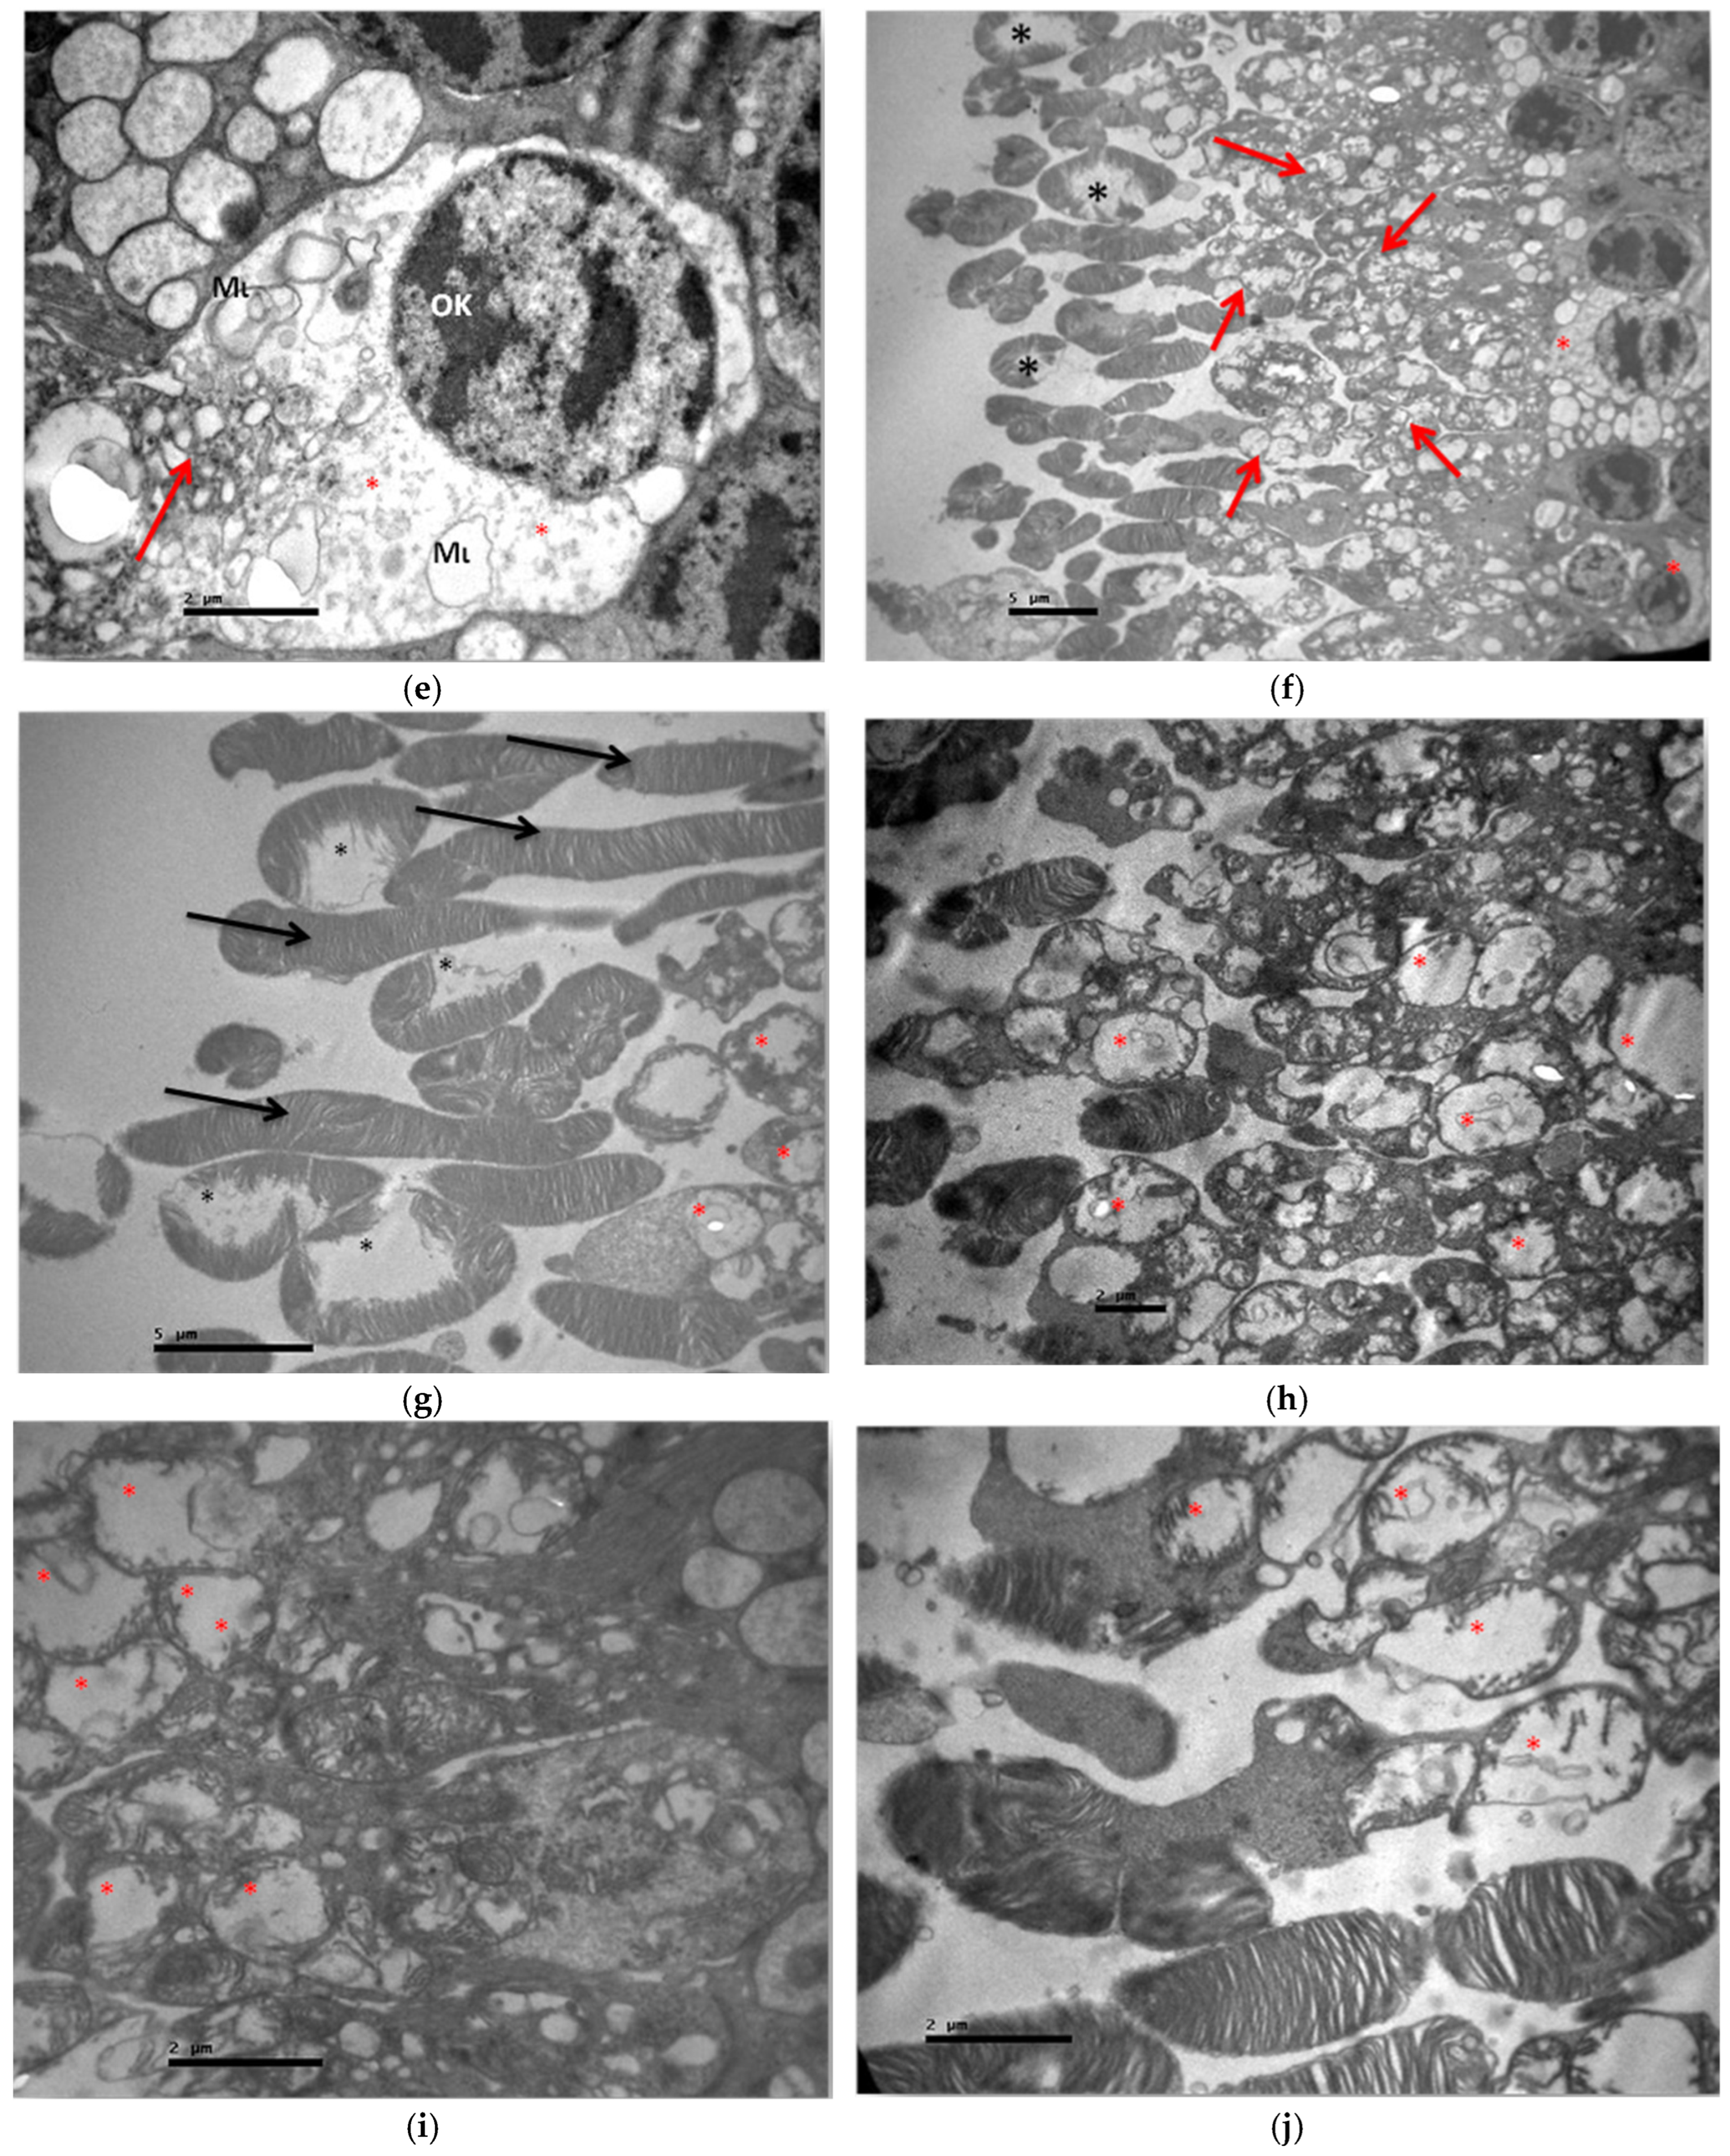

3.2.1. Group C2

3.2.2. Group V2

3.2.3. Group M2

3.2.4. Group VM